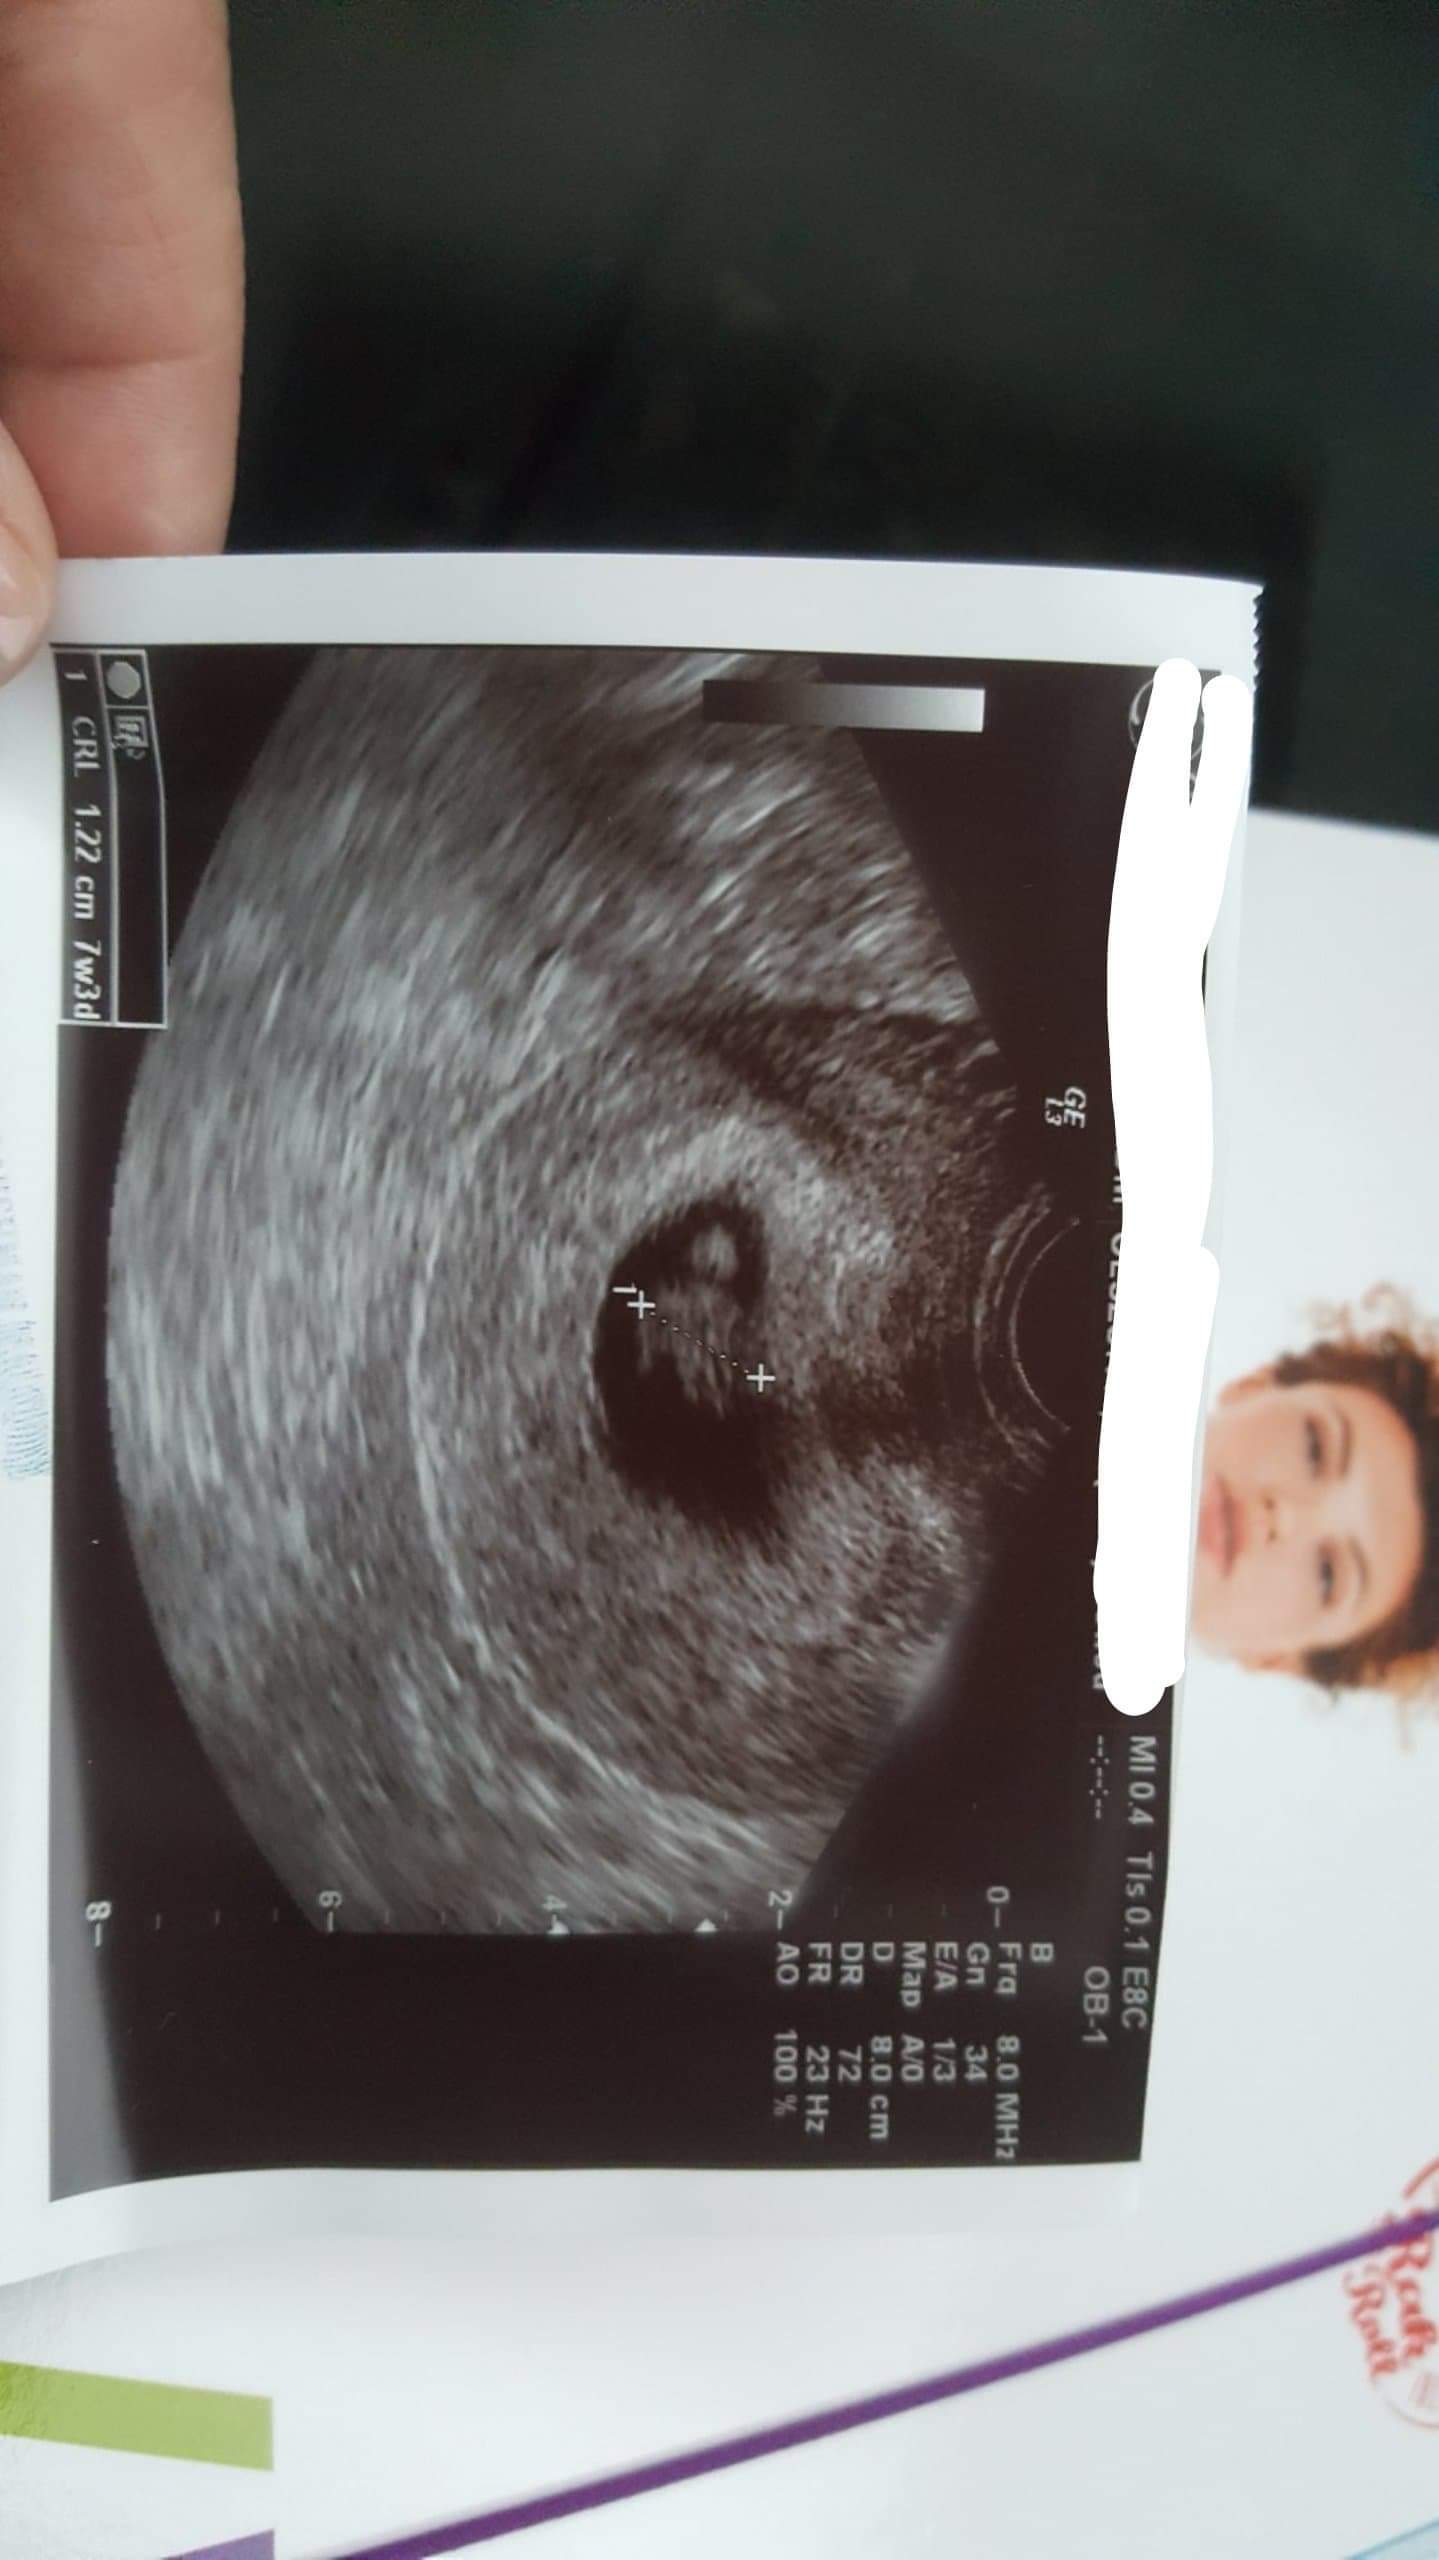

brawa dla Płodzia jest cudowny i uspokoiłaś mnie tym zdjęciem, bo widzę, że moj nie jest wcale za mały, a bardzo mi się tak wydawaloDziewczyny moj Płodzio rośnie, serduszko dalej bije ❤ Dostalam skierowanie na cytomegalie i rozyczke jutro będę robić![]()

Cudowne wiadomości! Niech Płodzio dalej zdrowo rośnieDziewczyny moj Płodzio rośnie, serduszko dalej bije ❤ Dostalam skierowanie na cytomegalie i rozyczke jutro będę robić![]()

Piękny PłodzioDziewczyny moj Płodzio rośnie, serduszko dalej bije ❤ Dostalam skierowanie na cytomegalie i rozyczke jutro będę robić![]()